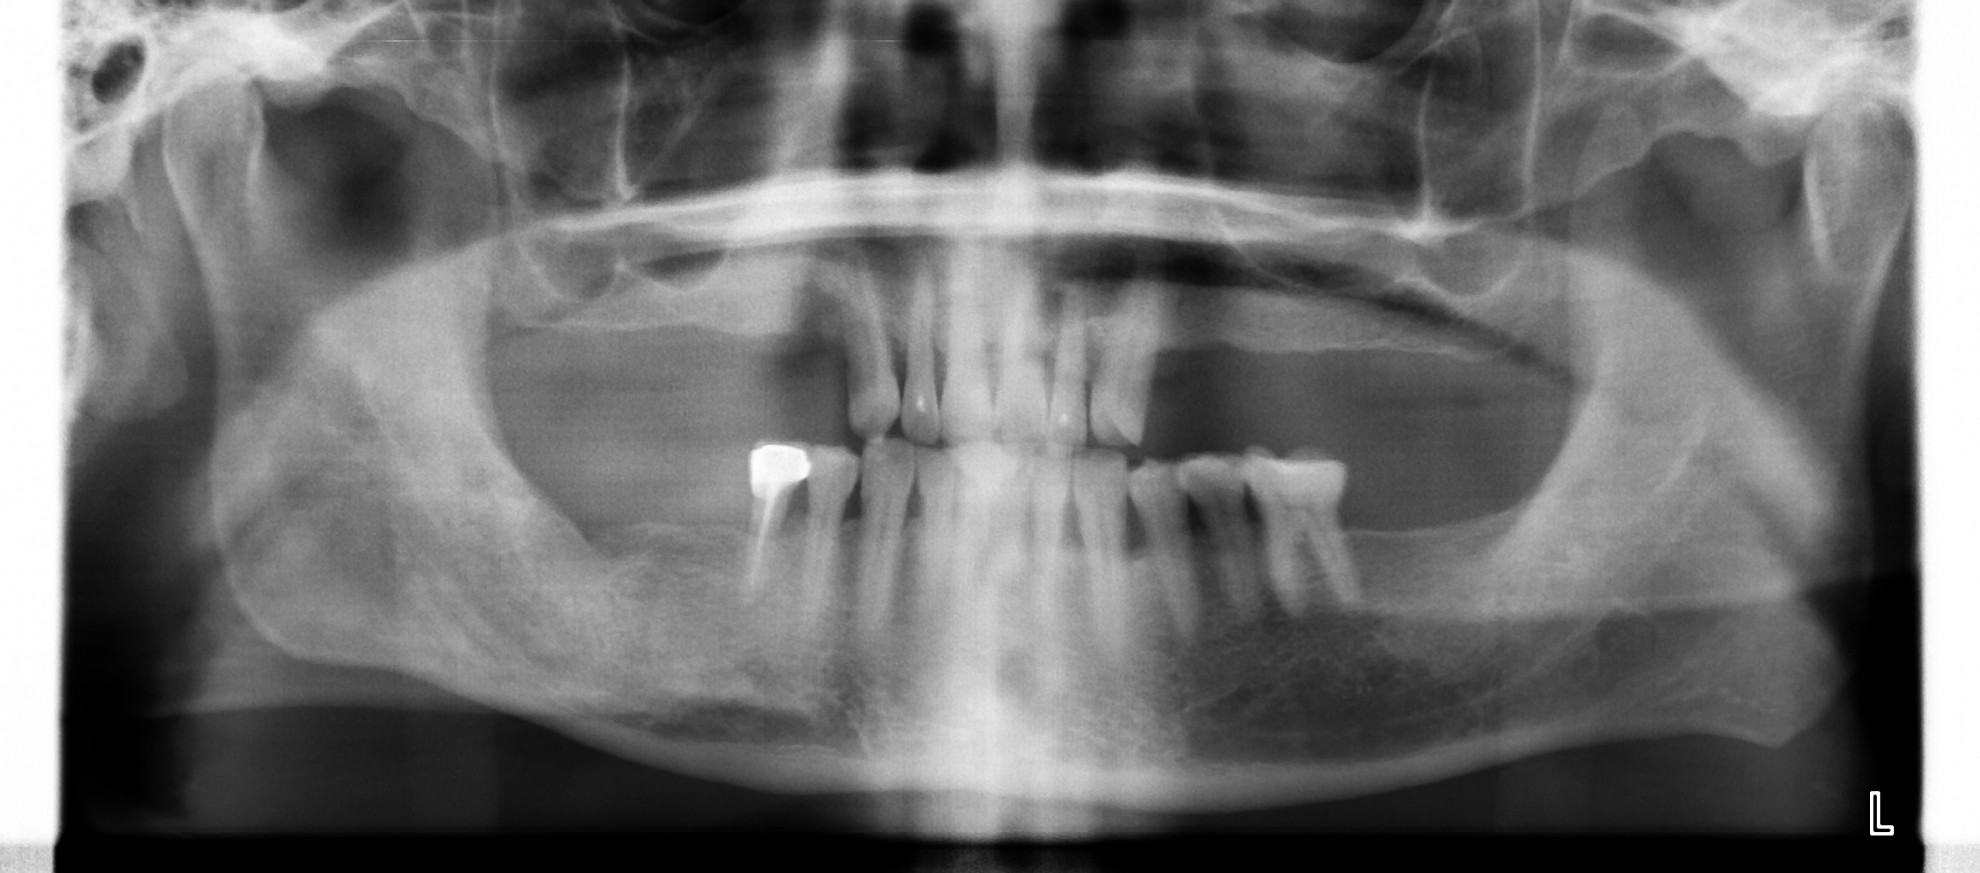

植牙重建合併側窗鼻竇增高 FT.江松岳醫師

此案例利用植牙建立病人缺牙區的咬合。右上後牙區域齒槽骨高度不足且鄰近鼻竇,採取側窗鼻竇增高術後植牙。